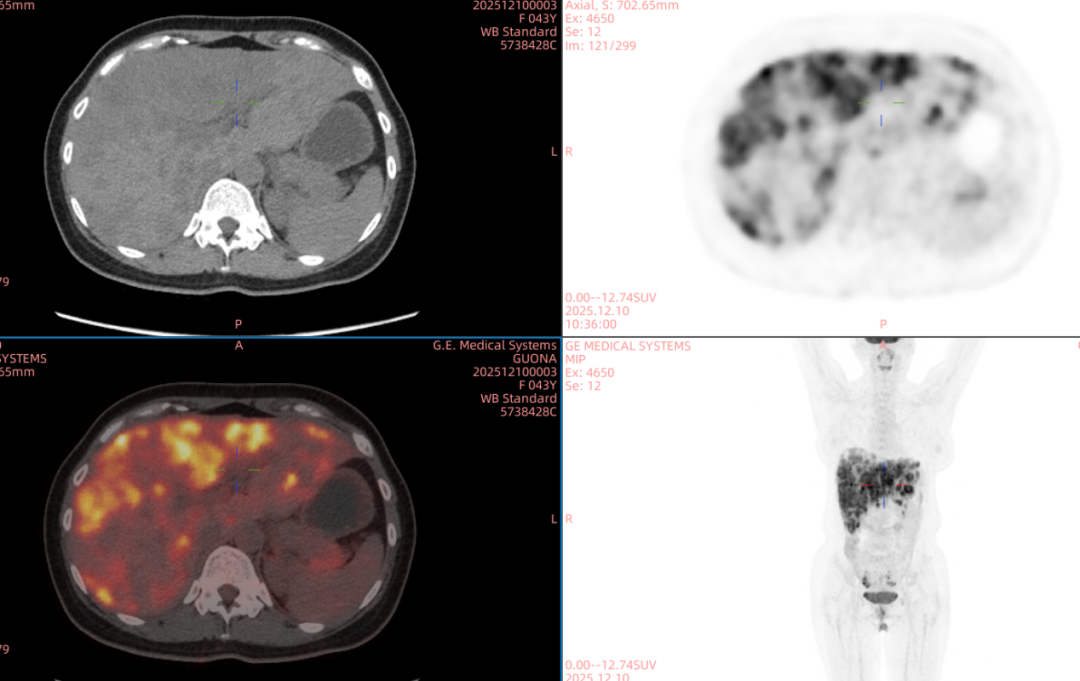

近日,甘肃省武威肿瘤医院武威重离子中心再迎新突破——全球首创双布拉格加重离子晶格放疗技术正式应用于临床。

“双布拉格”,并非指代两个物理峰值,而是两大核心治疗理念的深度碰撞与融合。第一个“布拉格”,是物理学范畴的布拉格峰——重离子束流可在体内特定深度释放绝大部分能量,这一特性构筑起“指哪打哪”、极致保护正常组织的物理基石。第二个“布拉格”,是免疫学范畴的布拉格治疗,即国际前沿的PRaG协同治疗方案。它通过精准放疗在局部“点火”,释放肿瘤抗原;以GM-CSF为“导航”,引导免疫系统识别肿瘤细胞;再借助PD-1抑制剂“解除免疫刹车”,让免疫细胞能够持久、全身性地攻击肿瘤,最终追求珍贵的“远隔效应”。而晶格放疗,正是连接两大“布拉格”理念的关键桥梁。针对常规手段无法照射的巨大肿瘤,它将均匀剂量场转化为无数离散的高剂量“能量岛屿”。这种模式不仅能奇迹般保护穿插其中的正常组织与脉管结构,其独特的剂量分布,更被证实可高效诱发免疫原性细胞死亡,将物理打击的能量,转化为激活全身免疫反应的“信号”,让肿瘤的局部治疗与全身控制成为现实。

四大优势协同发力:一,依托重离子射线特有的“布拉格峰”物理特性,实现对深部肿瘤的“定点爆破”;二,采用“晶格放疗”先进布野技术,在巨大肝肿瘤内部精准布设能量“棋盘格”,在高效杀伤肿瘤细胞的同时,为残存正常肝组织与关键脉管留存生存空间;三,将此次精准物理打击,完美嵌入“布拉格治疗”免疫协同策略,以此作为激活全身免疫反应的“点火器”,联合PD-1抑制剂与GM-CSF,力求激发远隔效应,对未被照射的病灶形成攻击;四,引入干细胞支持下的新一代免疫细胞疗法,整合诱导多能干细胞(iPSCs)或间充质干细胞(MSCs)来源的免疫效应细胞(如CAR-T、CAR-NK和TCR-T细胞)与工程化技术,提升癌症免疫治疗的可及性与疗效。